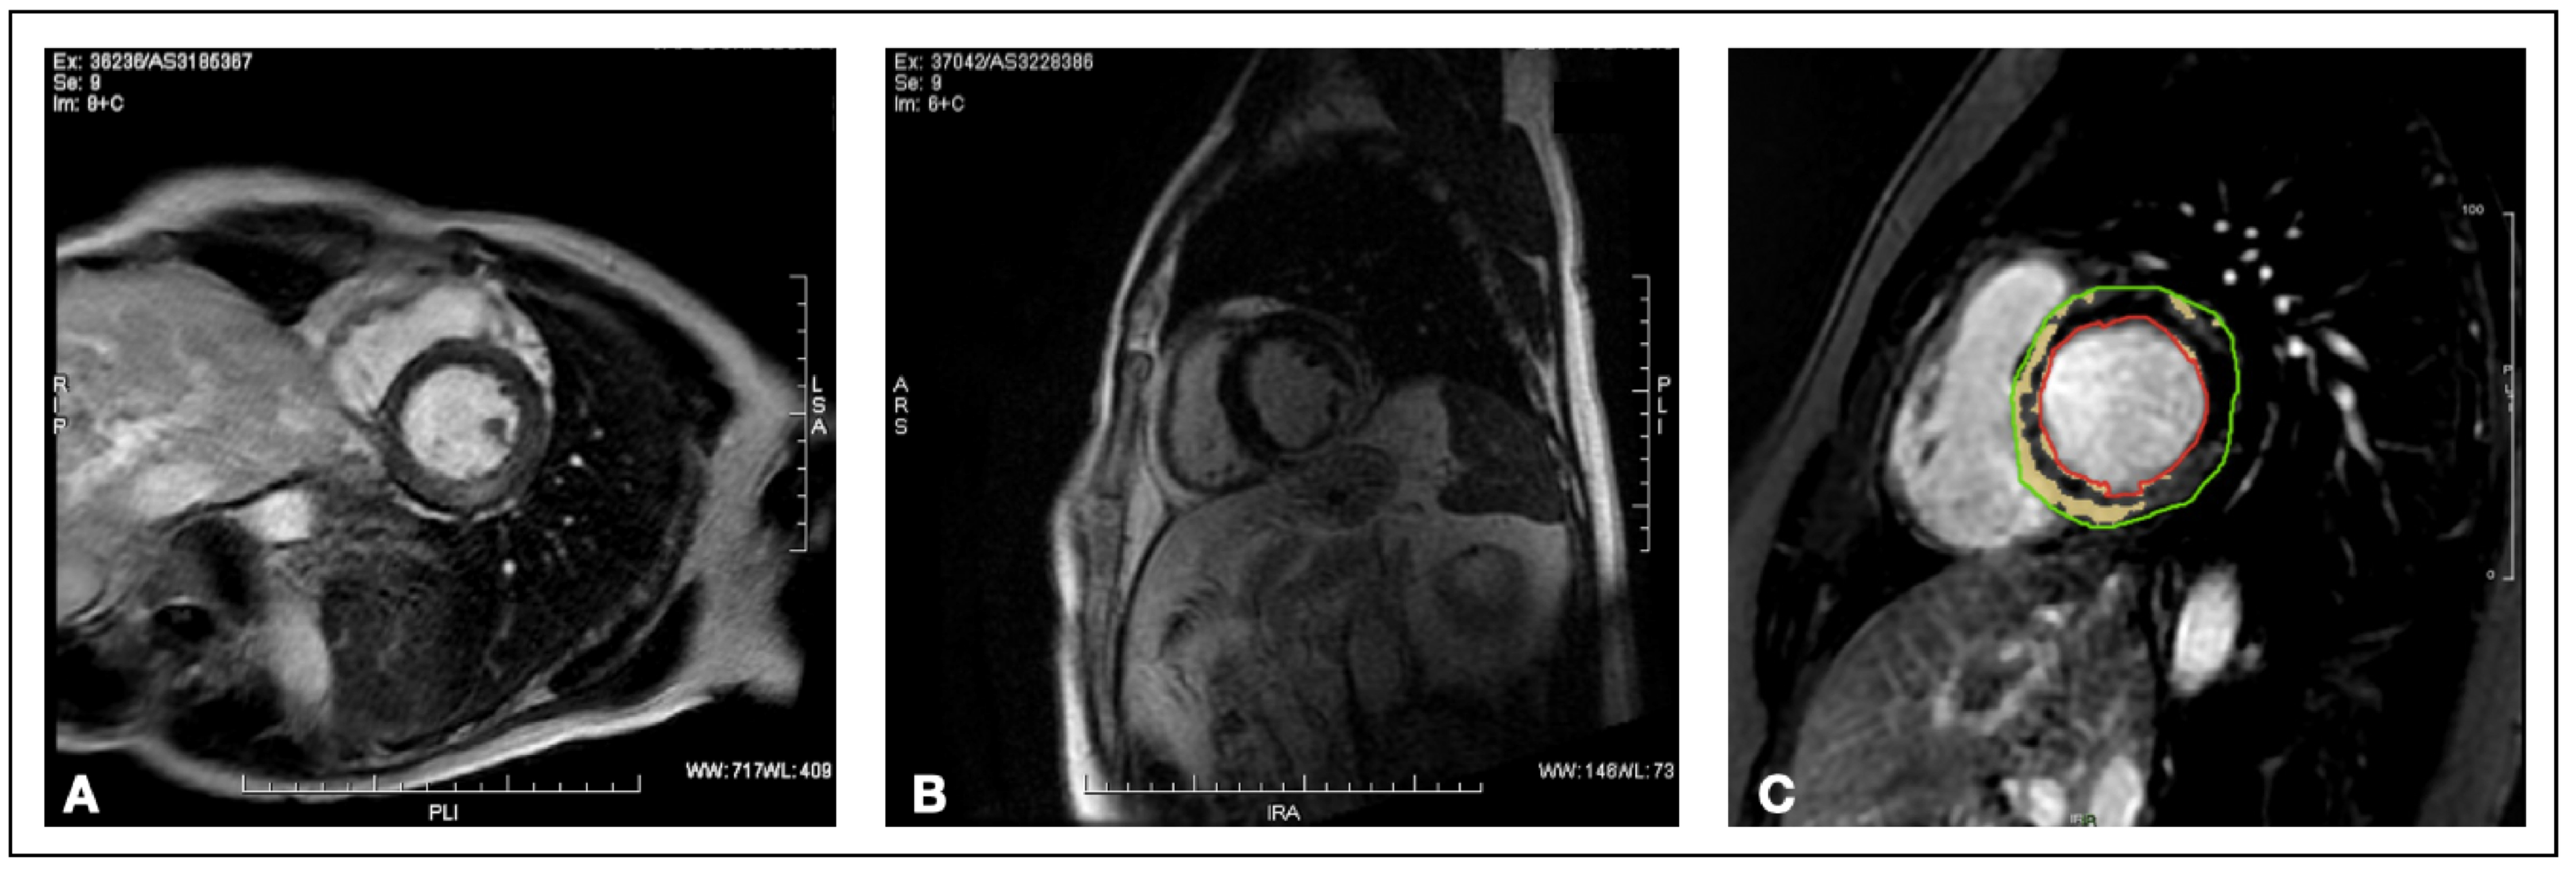

2.4. Cardiac Magnetic Resonance

2.5. Late Gadolinium Enhancement Quantification